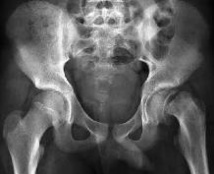

La prévalence de l'épiphysiolyse fémorale supérieure étant estimée à environ 2/100 000, cette pathologie sera rencontrée 1 à 2 fois dans l'exercice professionnel d'un médecin traitant, d'un pédiatre ou d'un radiologue.

Autant dire l'importance, quant on connait le long délai diagnostique de la forme chronique (5 mois !), de la connaître et de savoir quand la rechercher.